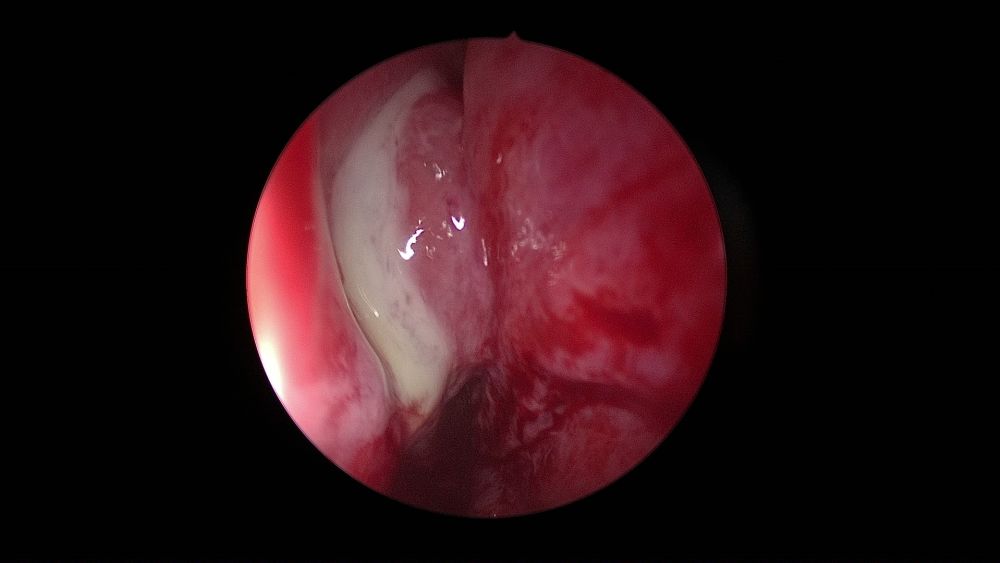

El pus en el meato medio (66-8%), seguido del edema del meato medio (34-43%) y pólipos (12-34%) han sido los hallazgos endoscópicos más comúnmente informados en la SO en diferentes estudios26 (Figura 2).

Desafortunadamente, los hallazgos de la endoscopia nasal por sí solos, no son específicos, ya que otras patologías de los senos nasales pueden tener hallazgos infecciosos en la endoscopia, y algunos pacientes con SO pueden tener endoscopias nasales normales14.